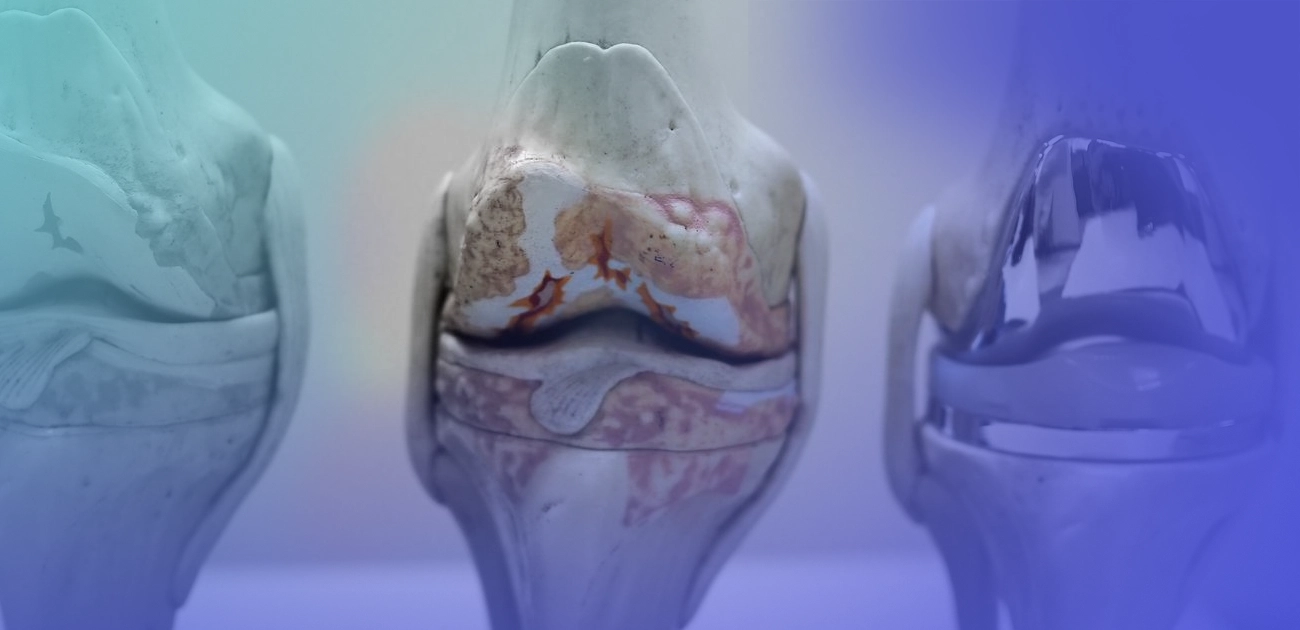

5 Mitos sobre Prótese de Joelho

A prótese de joelho é indicada apenas para pessoas idosas? Mito! A prótese de joelho é indicada para casos de

A prótese de joelho é indicada apenas para pessoas idosas? Mito! A prótese de joelho é indicada para casos de

A artroplastia do joelho, ou simplesmente cirurgia para colocação de prótese no joelho, é um procedimento de alta complexidade. Nesse